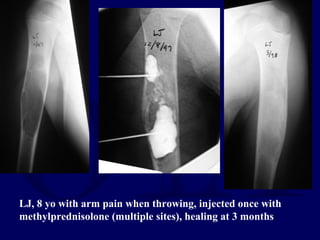

LJ, 8 yo with arm pain when throwing, injected once with

methylprednisolone (multiple sites), healing at 3 months